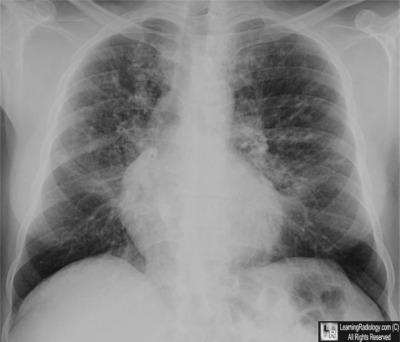

Bronchiolitis Obliterans Organizing Pneumonia - Wikipedia ...

Bronchiolitis obliterans organizing pneumonia (BOOP), also known as cryptogenic organizing pneumonia, The chest x-ray is distinctive with features that appear similar to an extensive pneumonia, with both lungs showing widespread white patches. ... Read Article